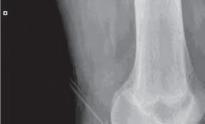

Podział złamań kości rosnących, tzw. złamań nasadowych: A – schematyczne przedstawienie klasyfikacji złamań; B – SH I (RTG, widok z przodu i z boku); C – SH II (RTG, widok z przodu i z boku); D – SH II (TK, widok z boku); E – SH III (RTG, widok z przodu i z boku); F – SH IV (RTG, widok z przodu i z boku); G – SH V (RTG, widok z przodu i z boku).

Rozpoznanie

Objawy złamania to silny ból uniemożliwiający stanie i chodzenie, zniekształcenie obrysów stawu kolanowego przez krwiak i różnego stopnia przemieszczenie nasady kości piszczelowej. Należy dokładnie zbadać stan ukrwienia i unaczynienia kończyny pod kątem objawów uszkodzenia tętnicy podkolanowej i nerwu strzałkowego. Trzeba ocenić bolesność uciskową oraz napięcie w przedziałach powięziowych podudzia: przednim, bocznym, tylnym powierzchownym i tylnym głębokim. U pacjentów z podejrzeniem wzmożonego ciśnienia wewnątrzprzedziałowego należy wielokrotnie powtarzać badanie ukrwienia i unerwienia kończyny, a w razie zaistnienia wskazań wykonać bezpośredni pomiar ciśnienia w przedziałach. Powinno się zawsze podejrzewać możliwość uszkodzeń więzadłowych współistniejących ze złamaniem. Badania obrazowe to RTG w pozycji AP, bocznej i skośnej. Wykonanie badania TK może być konieczne w celu pełnej oceny rozległości

złamania. W przypadku podejrzenia uszkodzenia tętnicy podkolanowej należy wykonać angio-TK lub arteriografię.

Leczenie złamania bliższej nasady piszczeli w przypadku uszkodzenia typu 1 i 2 według Saltera i Harrisa leczymy nieoperacyjnie. Należy wykonać zamkniętą repozycję i unieruchomić w opatrunku gipsowym udowym w zgięciu kolana 30–60°, zapewniającym najlepszą stabilność odłamów. Okres unieruchomienia wynosi od 6 do 7 tygodni. Po tym czasie usuwamy gips i zaczynamy ćwiczenia zwiększające zakres ruchomości stawu kolanowego oraz wzmacniające siłę mięśnia czworogłowego. Ważne jest, by prowadzić częste kontrole stanu ukrwienia i unaczynienia oraz kontrole radiologiczne w celu wykrycia ewentualnych przemieszczeń odłamów. Złamania pierwotnie niestabilne lub wtórnie przemieszczone wymagają zamkniętej repozycji stabilizacji drutami K. Typ 3 i 4

Złamania rzepki i podudzia

złamania według Saltera i Harrisa wymaga leczenia operacyjnego w postaci otwartej repozycji i stabilizacji śrubami. Należy unikać krzyżowania metalu zespalającego z chrząstką wzrostową. Kończynę zgiętą w kolanie do 30° unieruchamia się w gipsie udowym na okres 6–8 tygodni. Po tym czasie rozpoczynamy ćwiczenia czynne poprawiające zakres ruchomości kończyny.